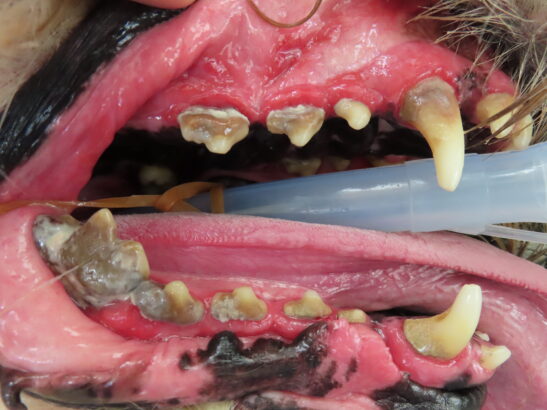

歯周病とは歯垢中の細菌が歯面に付着して、歯周組織(歯肉、セメント質、歯根膜、歯槽骨)が炎症を起こす病気です。

犬や猫の口の中の病気で最も多くみられるものが歯周病で、3歳以上の成犬・成猫の約80%が歯周病をもっていると言われています。

歯の表面や歯と歯肉の間に食べかすや唾液中の成分、被毛などがたまり、歯垢となります。歯垢には細菌も含まれ、その細菌が産生する毒素などによって炎症が起きます。歯肉が炎症を起こした状態を歯肉炎といいます。この時点で治療すれば完全に炎症はおさまります。しかし、これを放置すると歯肉以外の歯周組織にも炎症が及びます。これを歯周炎といいます。歯肉炎と歯周炎を総称したものを歯周病と呼びます。